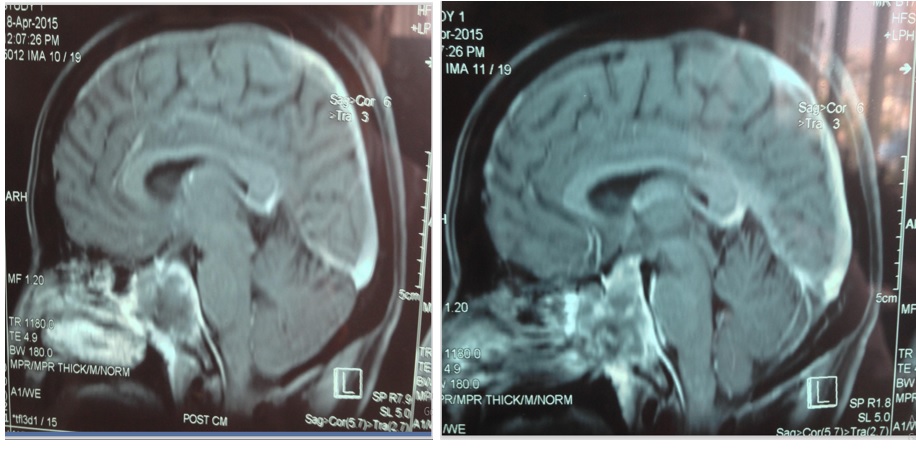

BN được chụp MRI xoang hang